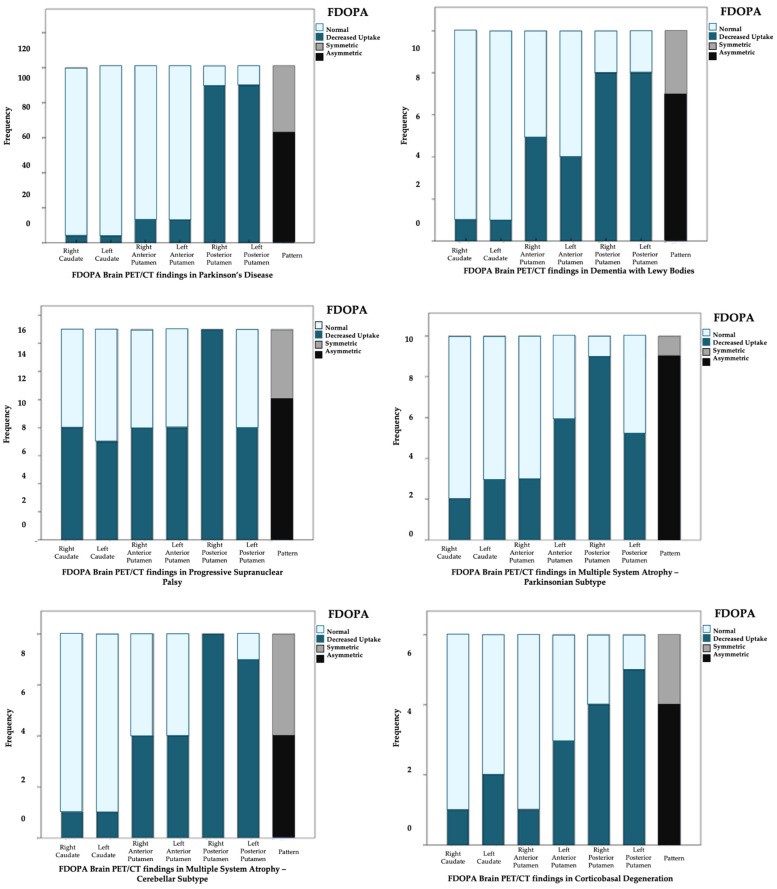

Among the 150 patients, 149 (99.3%) exhibited abnormal findings on FDOPA PET/CT. The most common abnormality observed was a reduction in uptake in the posterior third of the putamen nuclei, which occurred in 89.9% of cases. Only one patient had normal FDOPA PET results, with both clinical diagnosis and dual PET/CT suggesting DLB. An asymmetrical uptake pattern was the most common, seen in 65.1% (n = 97) of cases. Among the different Parkinsonisms, MSA-C was the only diagnosis that displayed both symmetrical and asymmetrical patterns. The asymmetrical pattern was most common in MSA-P (Scheme 1).

3.3. Brain [18F] FDG PET/CT Findings

Disturbances in glucose metabolism were observed in 47.33% of the patients. Normal metabolic findings were more frequent in patients diagnosed with PD, where overall normal cortical metabolism was observed alongside normal or hypermetabolism in the basal ganglia and hypometabolism in the parietal, occipital dorsolateral, and orbitofrontal cortex. In patients with atypical Parkinsonisms, metabolic alterations primarily affected the basal ganglia, with almost all cases presenting hypometabolism, except for DLB, where hypermetabolism in the striatum nuclei was also documented (Scheme 2).

3.4. Dual FDOPA–FDG PET/CT Diagnosis

The most frequent diagnosis provided by dual PET/CT was PD, identified in 67% (n = 101) of the patients. The remaining 33% were diagnosed with atypical Parkinsonisms: PSP in 10% (n = 15), DLB and MSA-P in 7% (n = 10) each, MSA-C in 5.33% (n = 8), and CBD in 4% (n = 6). The findings from FDOPA and FDG PET scans are summarized in Figure 1.

When analyzing the findings of PET/CT per radiopharmaceutical, we found that, regarding FDOPA, 149 out of 150 patients presented some type of alteration in the presynaptic dopaminergic pathway, with a greater defect in the posterior third of the putamen (89% of cases); the most frequent pattern was asymmetrical in 64.7%. The only Parkinsonism that exhibited a symmetric uptake defect pattern was MSA-C; on the other hand, only one patient with a clinical diagnosis of DLB showed integrity in the presynaptic dopaminergic pathway, although the uptake pattern on FDG PET was consistent with that of the clinical diagnosis. In 2020, Stormezand and collaborators reported data that supported the findings of decreased uptake on FDOPA PET in both idiopathic PD and atypical Parkinsonisms, with predominance in the posterior third of the putamen [ref. 20].

Nurmi and Brousolle reported in different studies that PD first shows alterations in the posterior putamen, followed by the anterior putamen and caudate nuclei, involving the side contralateral to the clinically affected one [ref. 23,ref. 24]. In our cohort, all PD patients presented a presynaptic dopaminergic pathway alteration; according to the literature, up to 10–20% of clinically diagnosed PD cases have shown integrity of the presynaptic dopaminergic pathway when evaluated by PET [ref. 25]. This situation can also occur with DLB, in which a study demonstrates that integrity of the presynaptic dopaminergic pathway does not rule out the diagnosis [ref. 26]; this is similar to the example mentioned above, where the diagnosis was established by the altered pattern in cerebral glucose metabolism, highlighting the importance of dual studies when clinical suspicious is high.

It has been described that in MSA-P, the pattern of decreased uptake with the FDOPA tracer is primarily evident in the caudate nuclei and anterior putamen [ref. 27]. This information differs from our findings, where, as mentioned earlier, the posterior putamen was the most affected. In the case of CBD, the alteration of the striatal nuclei on the side opposite to the clinically affected hemibody has been described [ref. 28], similar to our findings. Normal findings have also been reported; however, in our study, we did not have any normal findings in this pathology.

Regarding FDG PET/CT findings, 52.67% of patients showed preserved metabolism, which can be explained by the fact that most patients had a clinical and dual PET/CT diagnosis of PD, in whom cerebral glucose metabolism is generally preserved. Metabolic patterns with FDG have been useful in the differential diagnosis of PD, as well as in atypical Parkinsonisms [ref. 29,ref. 30]. These findings correspond with those described by Garraux et al., who concluded that FDG PET/CT accurately distinguishes between PD and atypical Parkinsonisms, a relevant factor for prognosis and treatment [ref. 31]. Figure 1 summarizes the findings from dual FDOPA and FDG PET/CT in our population; until now, this had not been characterized in Mexico, and the results were similar to published data.